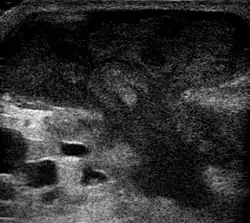

An abscess is a localized collection of pus (purulent inflammatory tissue) caused by suppuration buried in a tissue, an organ, or a confined space, lined by the pyogenic membrane.[31] Ultrasound imaging can help in a diagnosis.[32]